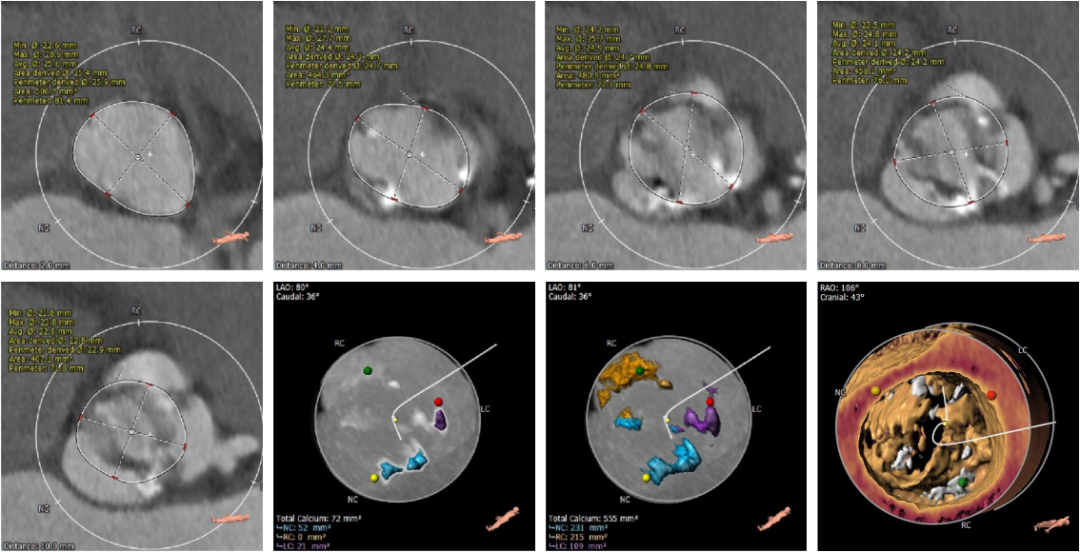

术前CT评估

CT结果显示,患者为Type1型二叶式主动脉瓣,中重度钙化合并瓣叶严重增厚。左右冠窦融合,瓣叶开口偏向一侧,钙化位置靠外侧近血管壁处,左右交界与左无交界发育不完全,形成纤维融合嵴并伴随少量钙化,瓣膜开口偏向右无对合缘侧。冠脉风险评估表明,左冠高度低,右冠高度可,左冠瓣长度大于冠脉开口与瓣叶附着缘距离,术中存在冠脉阻挡风险。综合瓦氏窦内径等因素考虑,瓣膜释放后,存在左冠状动脉阻挡风险,需术中球囊预扩时进行充分评估,必要时行冠脉保护。受钙化与瓣叶增厚影响,预估人工瓣膜形变较明显,释放过程中有潜在的下滑趋势。主动脉弓夹角锐利并弓距较短,也为这台手术增加入路和过弓难度。

主动脉根部及冠脉阻挡风险评估

瓣环上解剖结构及钙化程度分析